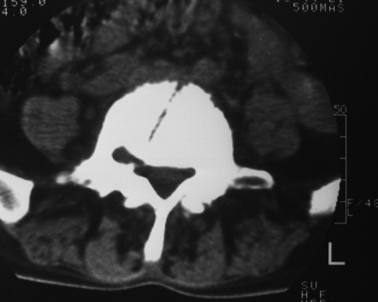

以下是引用dyqct在2007-3-1 18:04:00的发言:[br]腰5、骶1呈溶冰状骨质破坏,边界清楚,无明显硬化,内见多数沙粒状死骨,周围软组织肿胀。[br]考虑:腰5、骶1结核,建议严格抗结核治疗后复查。

以下是引用gaoxiao在2007-3-1 18:02:00的发言:[br]腰5骶1椎体见骨质破坏,其内见死骨形成,椎前软组织肿胀,感染性病变,腰骶椎tb。

以下是引用gaozhengyi在2007-3-1 19:39:00的发言:[br]骨质破坏并砂砾样死骨为椎体结核的表现。椎体结核骨质破坏区的特点是呈虫蚀状,常可见硬化缘。死骨表现为片状高密度影,正如本例。